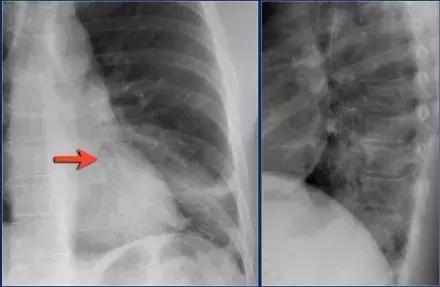

肺隔离症

肺隔离症是肺叶实变不常见的原因,属于先天性异常。

➢ 肺部肺功能部分不能和支气管树进行正常的信息传递,无法接受体循环提供的动脉血。

➢ 当细菌从孔氏孔移动时,病人会出现反复感染

➢ 箭头所示为从主动脉分离的供血动脉

图8 肺隔离症实变